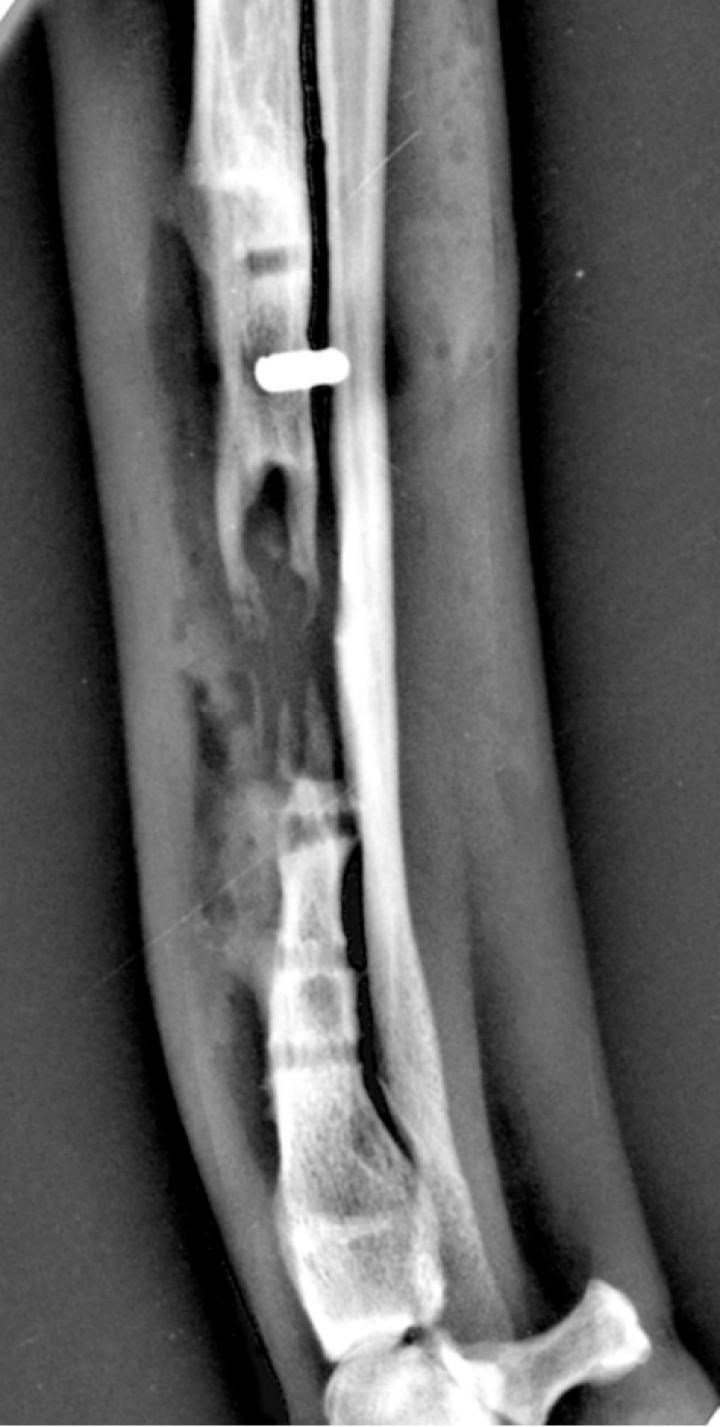

Se llevaron a cabo radiografías de la extremidad, en las que se observó una disminución de la densidad ósea en la zona del implante (Fig. 1).

<p>Radiografía mediolateral que muestra la desmineralización y defecto óseo en la zona subyacente al implante secundarios a la osteomielitis, correspondiente al día de la primera consulta (día 48).</p>

Radiografía mediolateral que muestra la desmineralización y defecto óseo en la zona subyacente al implante secundarios a la osteomielitis, correspondiente al día de la primera consulta (día 48).